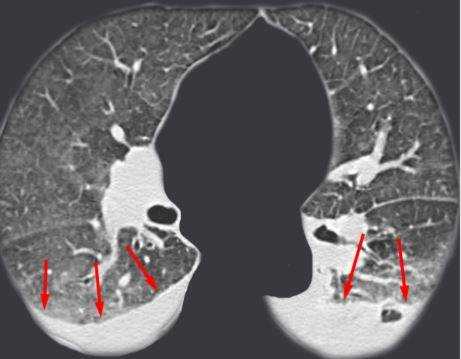

![Туберкулез на снимке МРТ]()

Туберкулез на снимке МРТ (стрелками показаны очаги в паренхиме легких (а) и туберкулезный плеврит (b))

Туберкулез на КТ, как и на МРТ, диагностируют по основным признакам заболевания. Чаще других во время процедуры визуализируют на снимках:

- уплотнение легочной ткани - один или несколько очагов поражения рядом с бронхами;

- увеличенные лимфоузлы у корня легкого и средостения.